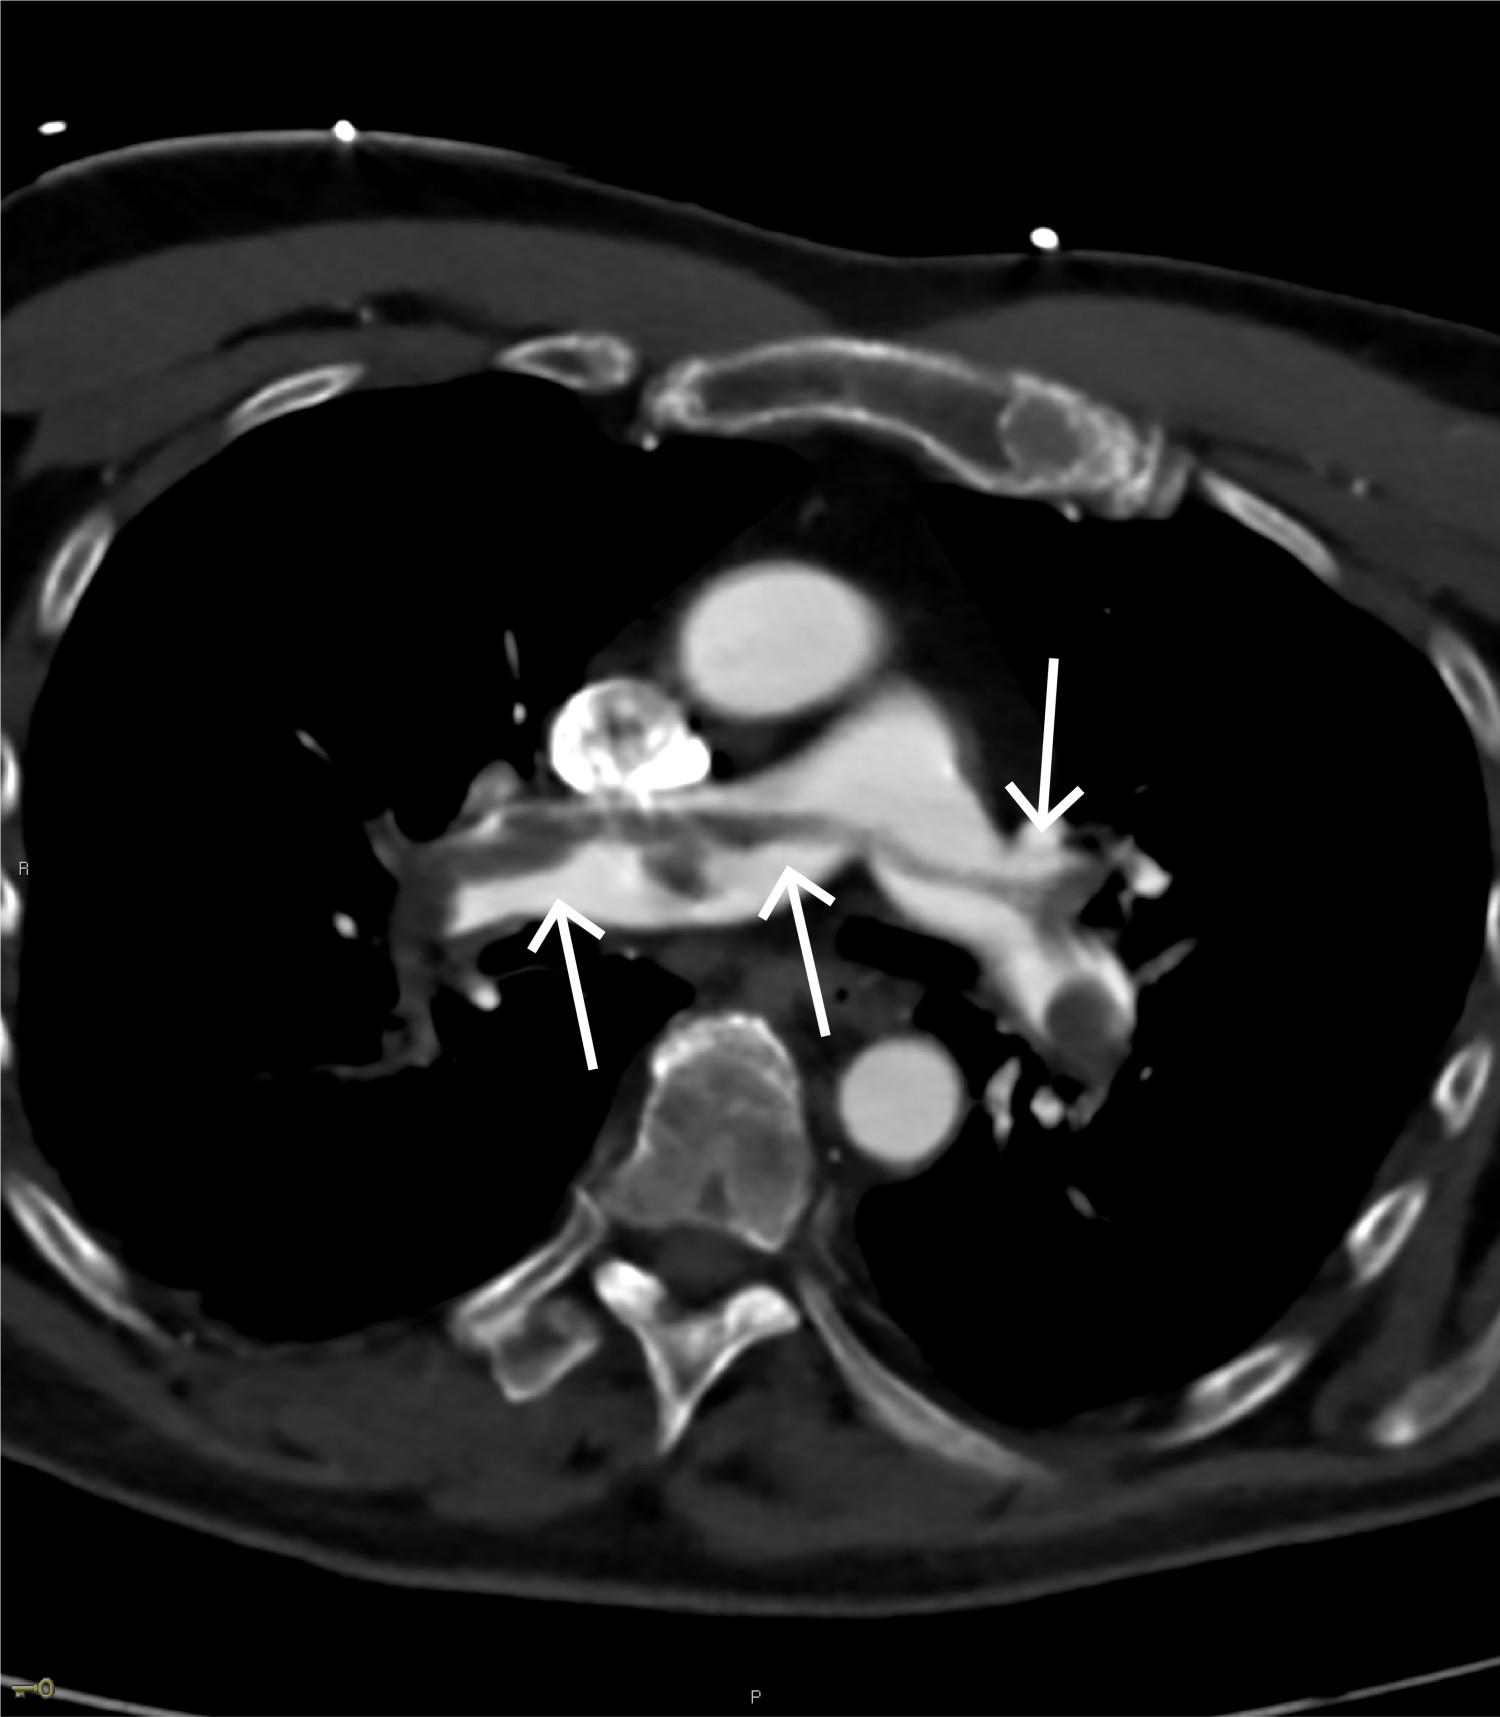

CT toraks med lungeemboliprotokoll viste sadelemboli, med tromber ut i de fleste større lungearterier og med affeksjon av alle lungelapper på lobært og segmentalt nivå (figur 4 og 5). Størst utfall var i underlapper. Aortadisseksjon ble ikke påvist.